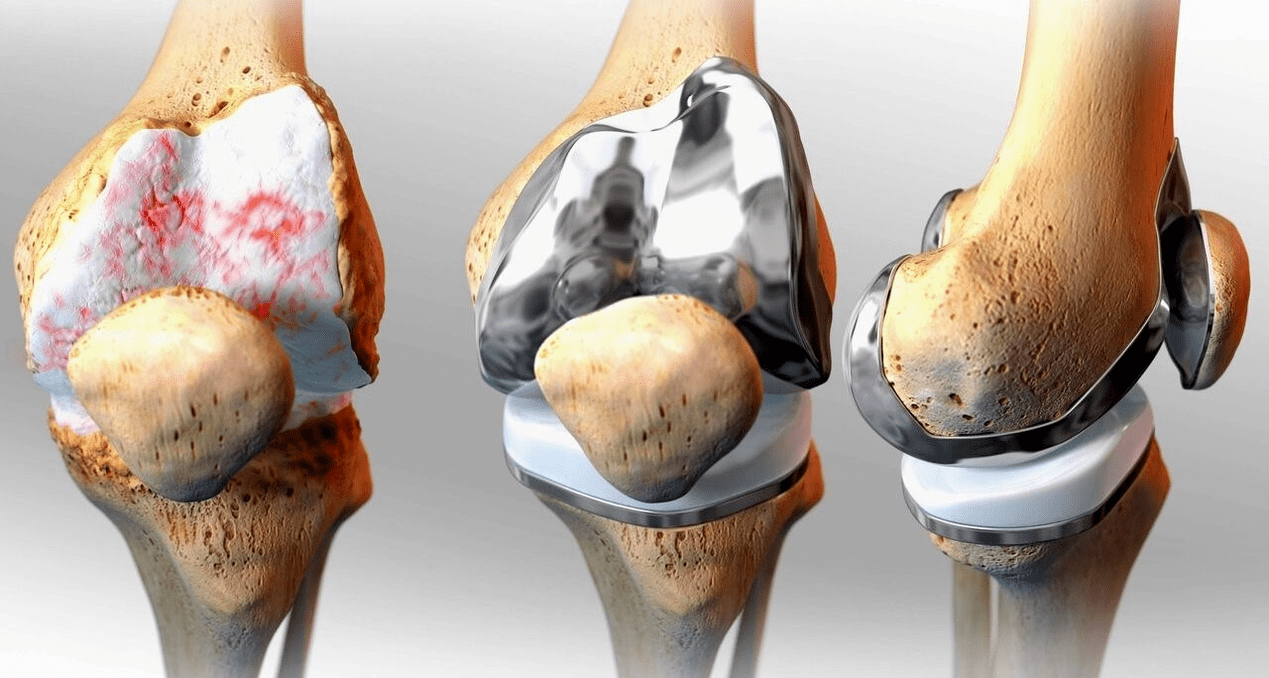

Trattamento chirurgico ed endoprotesi

La sostituzione dell'endoprotesi è un metodo chirurgico comune ed efficace per il trattamento della gonartrosi grave, che consente di mantenere la mobilità degli arti e la capacità di condurre successivamente una vita piena. Si tratta di un'operazione ad alta tecnologia della durata di circa un'ora e mezza. Nel periodo postoperatorio sono necessari la riabilitazione e lo sviluppo dell'articolazione a lungo termine. Dopo 25-30 anni, quando l'articolazione artificiale si usura, è necessario sostituirla nuovamente.